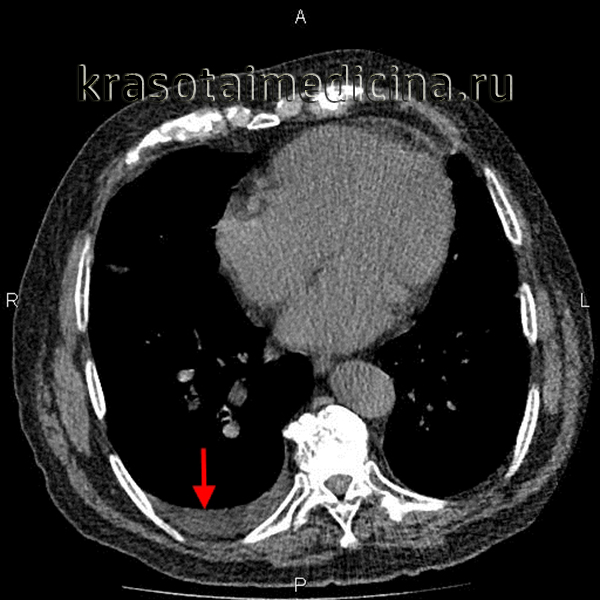

- Рентген. Полипозиционная рентгенография и рентгеноскопия легких при эмпиеме плевры обнаруживают интенсивное затенение. Для уточнения размеров, формы осумкованной эмпиемы плевры, наличия свищей выполняют плеврографию с введением водорастворимого контраста в плевральную полость. Для исключения деструктивных процессов в легких показано проведение КТ, МРТ легких.